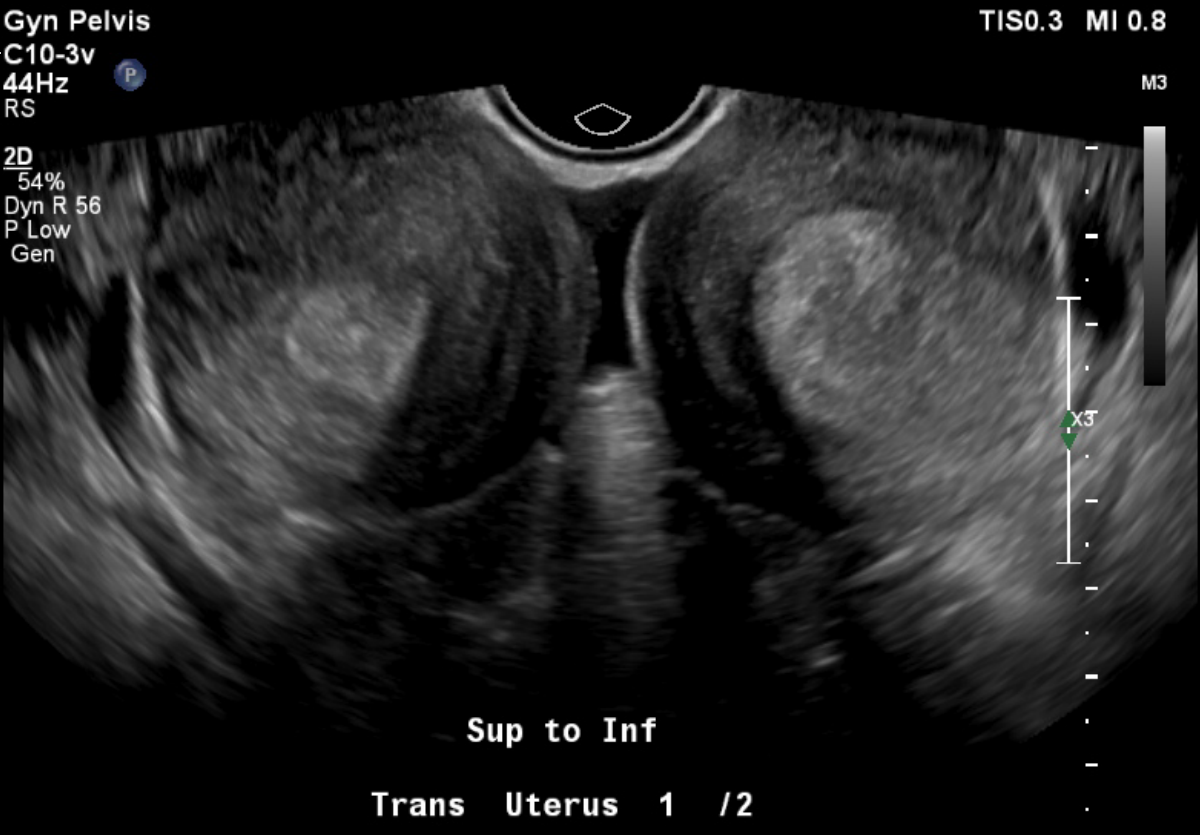

While opsoclonus-myoclonus-ataxis (dancing eye-dancing feet syndrome) may seem rare and complex, its early identification in the ED can be life‑altering. When faced with an unusual movement disorder a